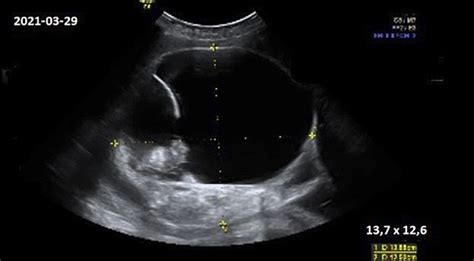

- Ultragarsinis tyrimas: Tai tiksliausias metodas, leidžiantis ne tik nustatyti vaisiaus poziciją, bet ir įvertinti vaisiaus vandenų kiekį, placentos vietą bei galimus apsivertimo barjerus.